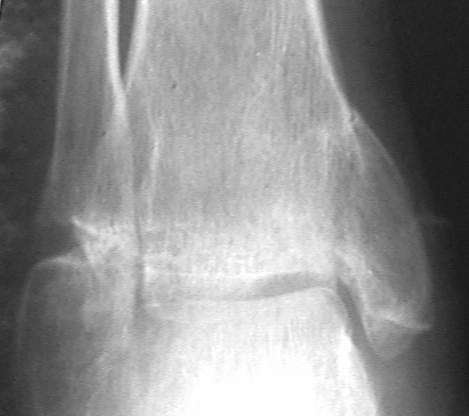

У больного травма в августе 2001 г. Лечился консервативно, Проводилась иммобилизация гипсовой лонгетой 3 мес. В последующем местное лечение. Остается контрактура боли в области наружной лодыжки. Направлен в наше отделение в конце января 2002 г Планируется костная аутопластика, остеосинтез пластиной, винтами перелома наружной лодыжки. Решается вопрос о коррекции неправильно сросшегося перелома внутренней лодыжки. Рентгенограммы: фас; профиль; план Сергей Зырянов

Надо сделать компьютерную томография и объектизировать истинное состояние переломов лодыжек. Пока не видно подвывиха таранной кости, а ложный сустав внутренней лодыжки (я его не вижу)в основном не вызывает функциональных растройств в голеностопном суставе.

Коллеги! Я думаю надо плясать от возраста, профессии, объёма движений и интенсивности болевого синдрома. Ничего подобного не прозвучало... Имеет место подвывих стопы кнутри, никем не отмеченный! Оно конечно варус лучше, чем вальгус, но в данном случае принципиально его устранение (если оперировать конечно). Если оперировать, то предлагаю: